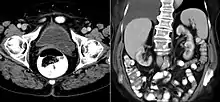

CT scan showing a ureterocele associated with a duplicated collection system of the left kidney.